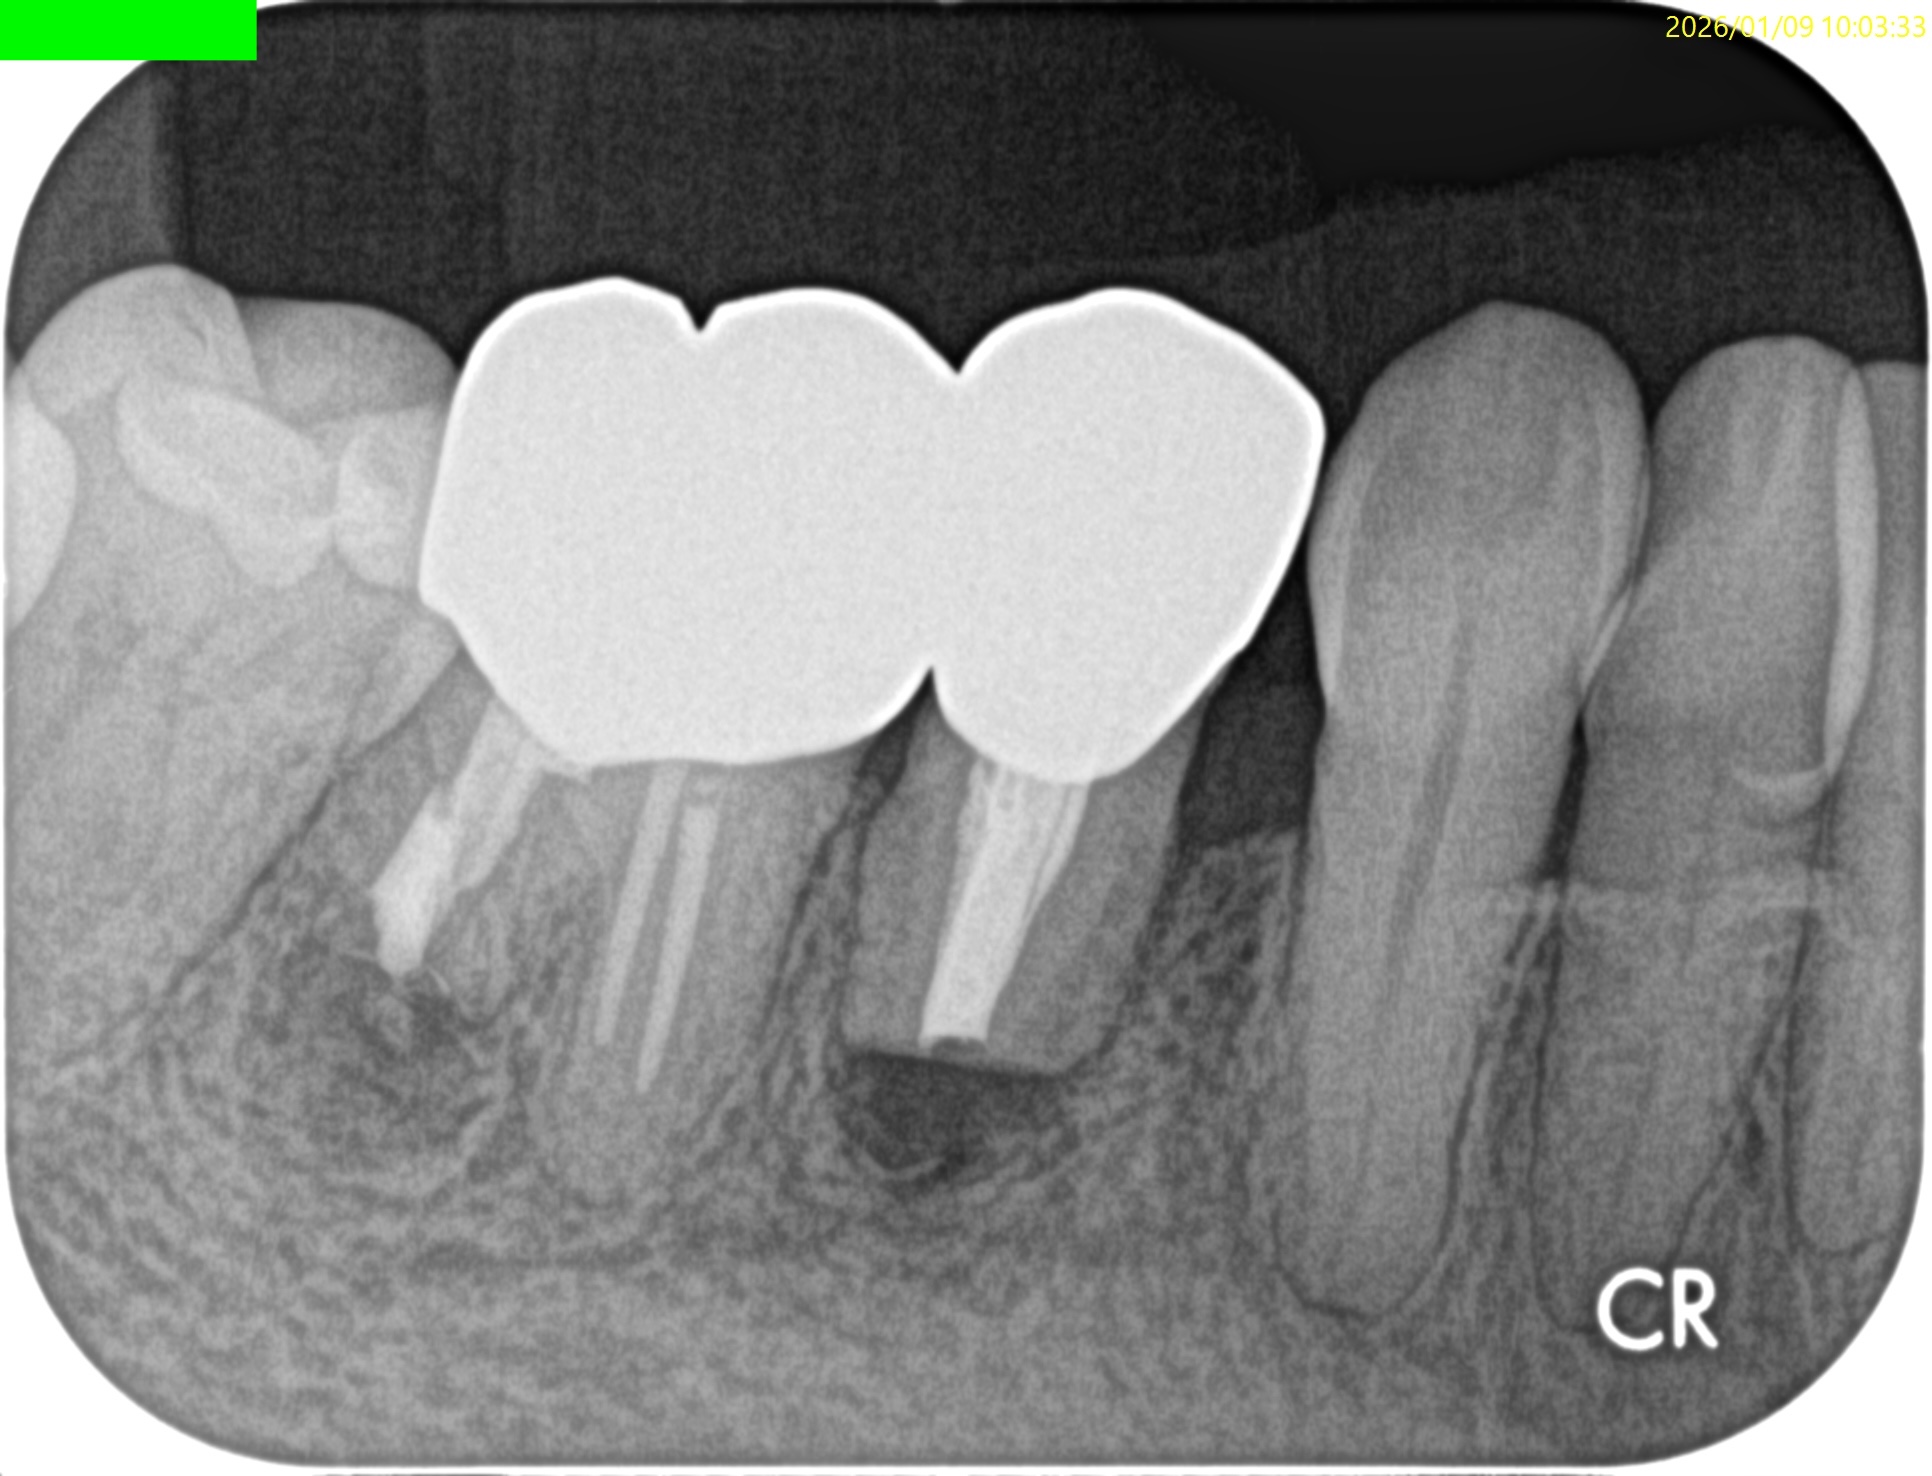

#30 D Apicoectomy 3M recall(2026.1.9)

#30の術前の圧痛が消失していた。

PAの感じもだいぶ変わっていた。

CBCTも撮影している。

歯槽骨も回復傾向だ。

このまま経過を見ていく。